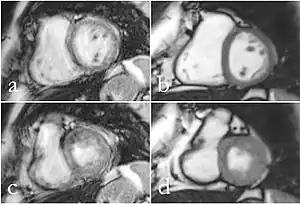

(a,c) CINE and (b,d) RT CMR at 1.5 T of a patient with atrial fibrillation in a mid-ventricular SA view during end-diastole (a,b) and end-systole (c,d). CINE mages have reduced diagnostic quality (score 1), while RT images present with good diagnostic quality.

Cardiac MRI

Although applications of real-time MRI cover a broad spectrum ranging from non-medical studies of turbulent flow[26] to the noninvasive monitoring of interventional (surgical) procedures, the most important application making use of the new capabilities is cardiovascular imaging.[1] Previous cardiac MR (CMR) used cine techniques to capture the periodic motion of the heart. However, this is not feasible for patients with arrhythmia, where the cardiac cycle is unpredictable.[27] With the new method it is possible to obtain movies of the beating heart in real time with up to 50 frames per second during free breathing and without the need for a synchronization to the electrocardiogram.[28] A study performed by Laubrock et al.[27] demonstrated that RT-MRI produced higher quality images with a higher SNR than cine CMR with a bSSFP sequence and radial k-space sampling. RT-MRI also removes the need for breath-holding while imaging, leading to a more comfortable experience for the patient as well.[27]